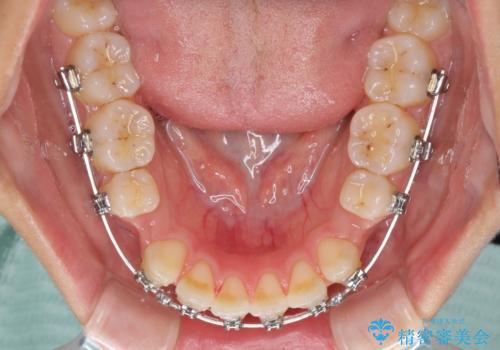

- 矯正装置

- メタルブラケット

受け口傾向の方の下顎抜歯矯正では、下顎前歯の歯肉が退縮することがあります。前歯を移動させるときには、歯肉退縮が起こらないように工夫する必要があります。